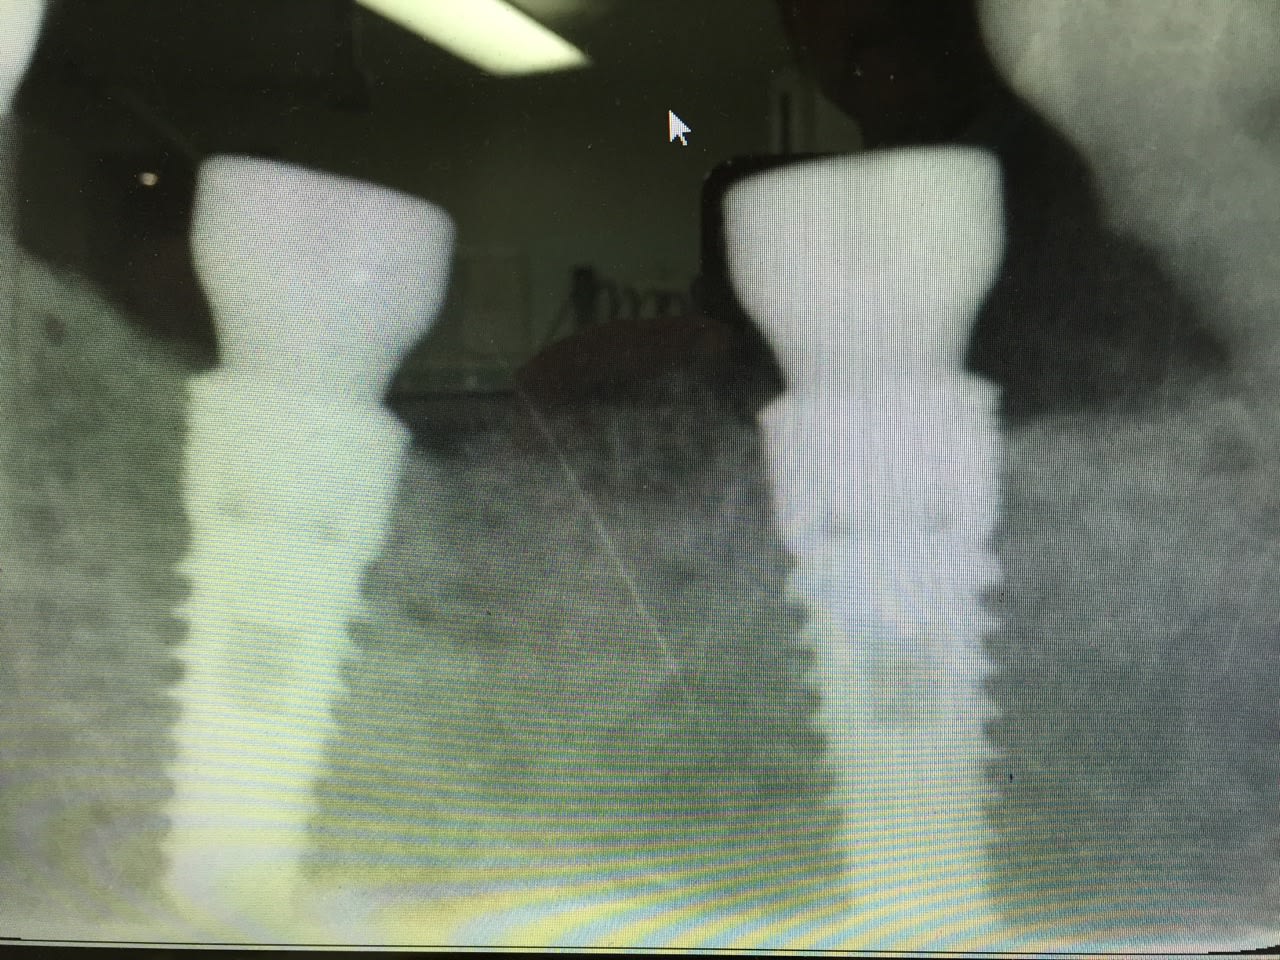

avez vous une idée pour l'identification de ces deux implants

Facile, Naturall ETK

https://www.etk.dental/fr/produits-et-solutions/implant-naturall/